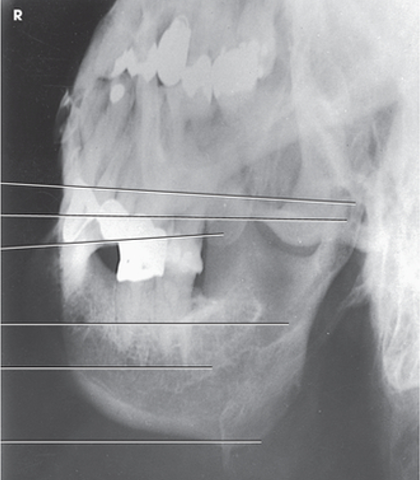

what anatomy is this?

symphysis

body

coronoid process

ramus

condyle

petrous ridge